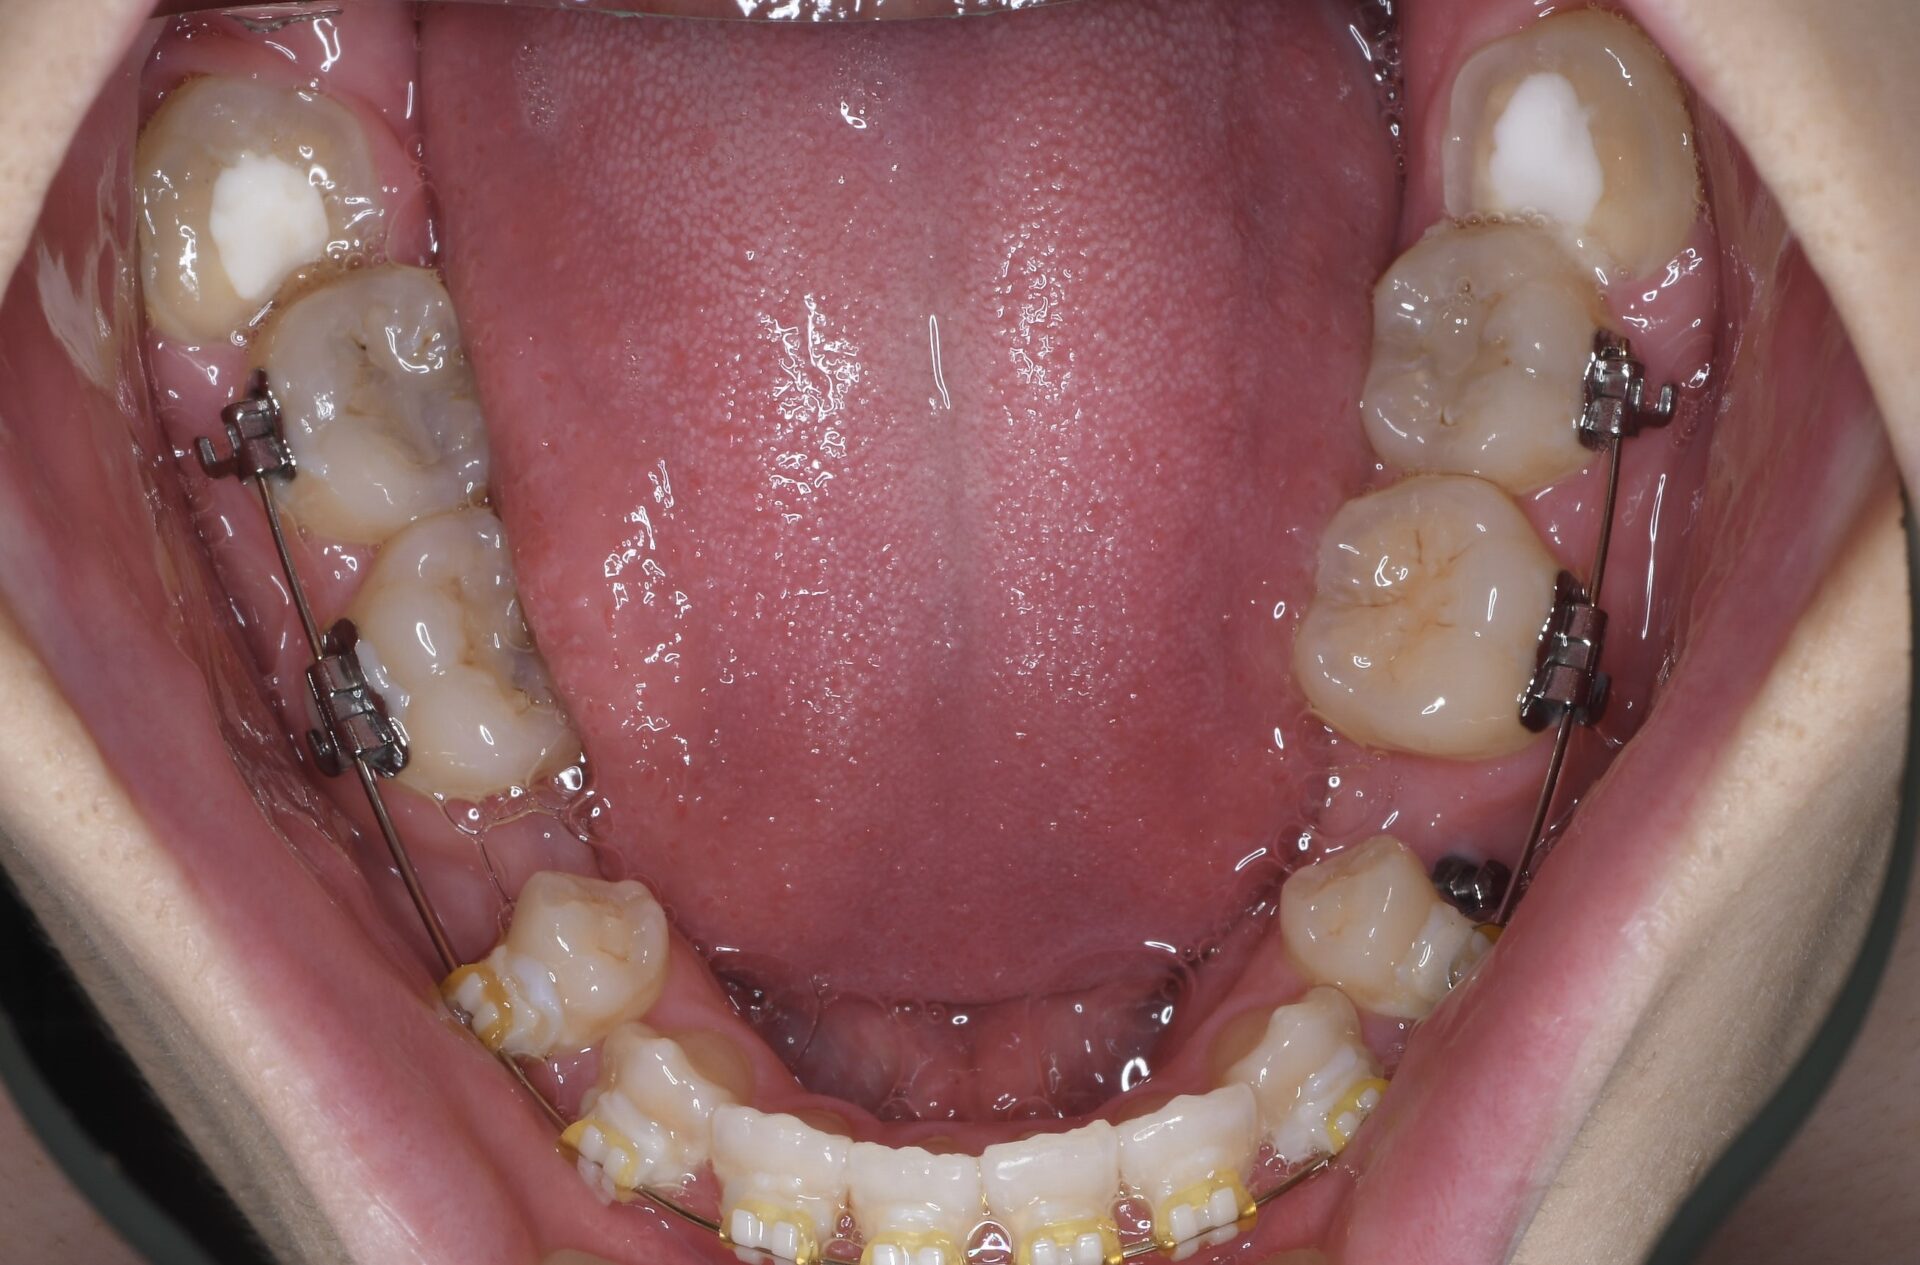

矯正治療スタート時(下顎) 左右第2小臼歯は先天的に欠損。智歯の根尖は下歯槽菅神経に触れているため歯冠を落とし、智歯の神経の処置をして少しずつ上に移動して下歯槽管神経から離れるのを待つ。

メインテナンス時(下顎)